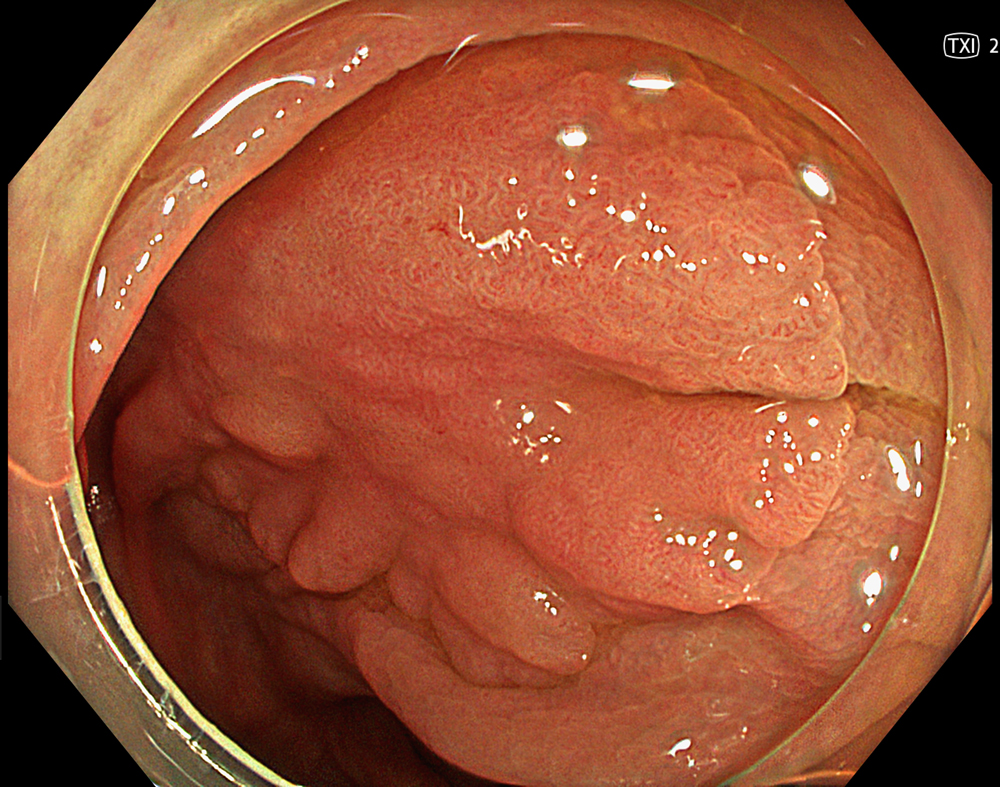

2. LST-NG with TXI (Mode 1)

TXI mode 1 enhances the lesion by combining texture, brightness, and color tone enhancement, improving visualization of surface structure and lesion margins compared with white light imaging.

Enhancement : A8

NBI Mode : NA

TXI Mode : Mode1

RDI Mode : NA

BAI-MAC : On